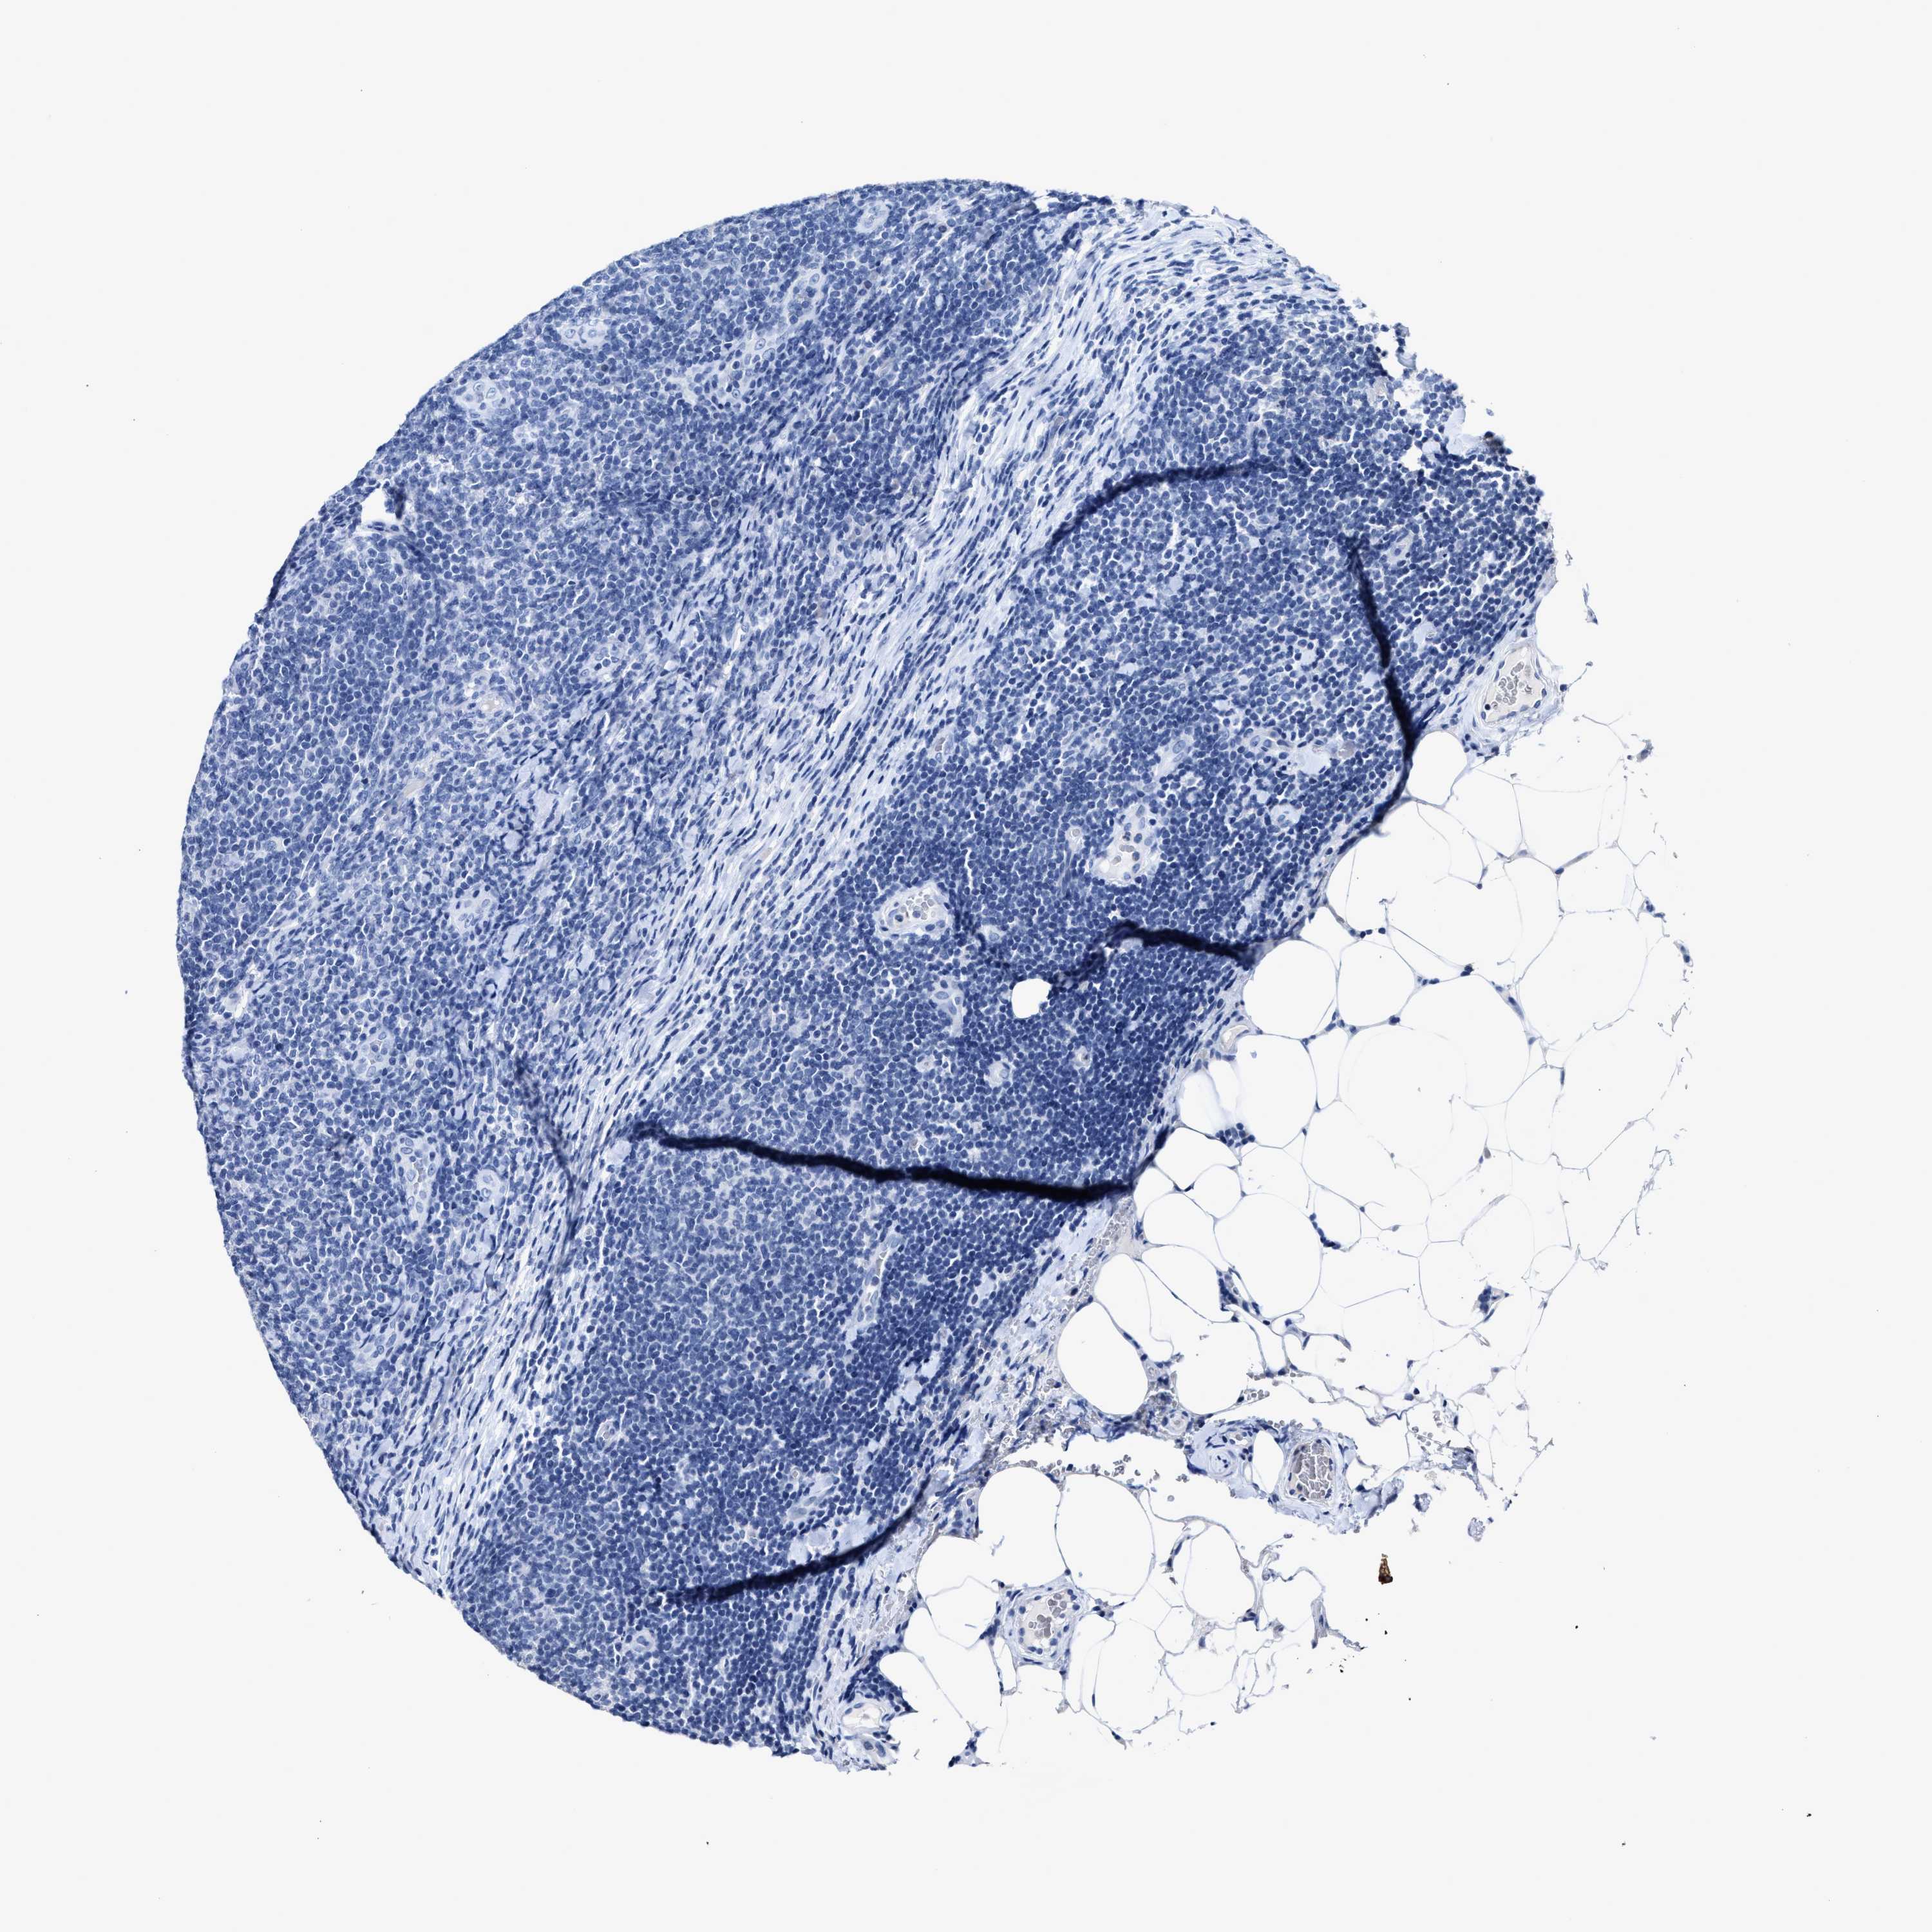

LYMPHOMA - Protein expressioni

A mouse-over function shows sample information and annotation data. Click on an image to view it in a full screen mode. Samples can be filtered based on level of antibody staining by selecting one or several of the following categories: high, medium, low and not detected. The assay and annotation is described here.

Each image is clickable and will lead to virtual microscopy that enables deeper exploration of all samples and also displays staining intensity scores, fraction scores and subcellular localization as well as patient and tissue information for each sample.

Antibody HPA019758

Hodgkin's disease, NOS

Malignant lymphoma, non-Hodgkin's type, Low grade

Malignant lymphoma, non-Hodgkin's type, High grade